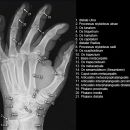

Hand a.p. (dorsovolar)

Beurteilungskriterien

• Kontinuität der drei Karpalbögen (vgl. Handgelenk):

Proximaler Bogen: proximale Gelenkflächenkonturen von Scaphoid, Lunatum und Triquetum

Mittlerer Bogen: distale Gelenkflächenkonturen von Sacphoid, Lunatum und Triquetum

Distaler Bogen: proximale Gelenkflächenkonturen von Capitatum und Hamatum

Fehlende Abgrenzbarkeit, Versatz oder Unterbrechung sind als pathologisch zu bewerten und deuten auf eine Luxation hin.

• M-förmiger Verlauf der Gelenkspalten der Carpometacarpalgelenke? Luxationsstellung in den Carpometacarpalgelenken (meist dorsale Luxation)?

• Gelenkspaltweiten der Carpometacarpalgelenke, der Metacarpophalangealgelenke und Interphalangealgelenke 1 –2mm, der Intercarpalgelenke 1,5 – 2mm

• Täuschungsmöglichkeiten durch Vielzahl akzessorischer Ossikel (abgerundete, zirkulkär-geschlossene Kortikalis), geteilte Handwurzelknochen (Scaphoid, Lunatum, Pisiforme) und Gefäßkanälchen

• Target areas leicht zu übersehender Frakturen:Processus styloideus radii et ulnae, Basen der Metacarpalia (v.a. MCP I) -> großzügige CT-Indikation, Hamulus

Cave: Metacarpale und phalangeale Rotationsfehlstellungen sind konventionell röntgenologisch schwer zu diagnostizieren und zu quantifizieren -> klinischer Befund führend (Fingerstrahl kreuzt bei Beugung im Grundgelenk den benachbarten Strahl), evtl. CT hilfreich.